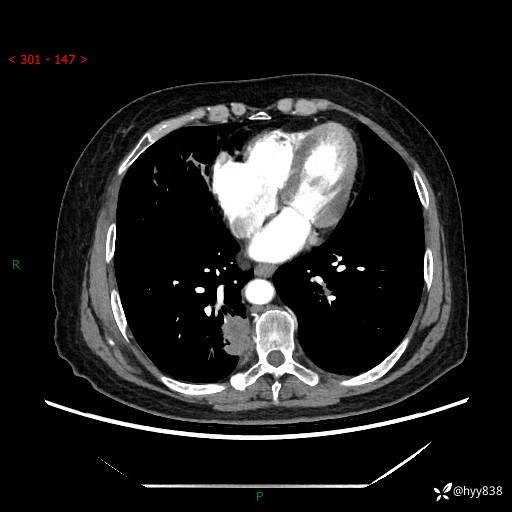

增强动脉期+静脉期

两期CT值:55Hu 53hu